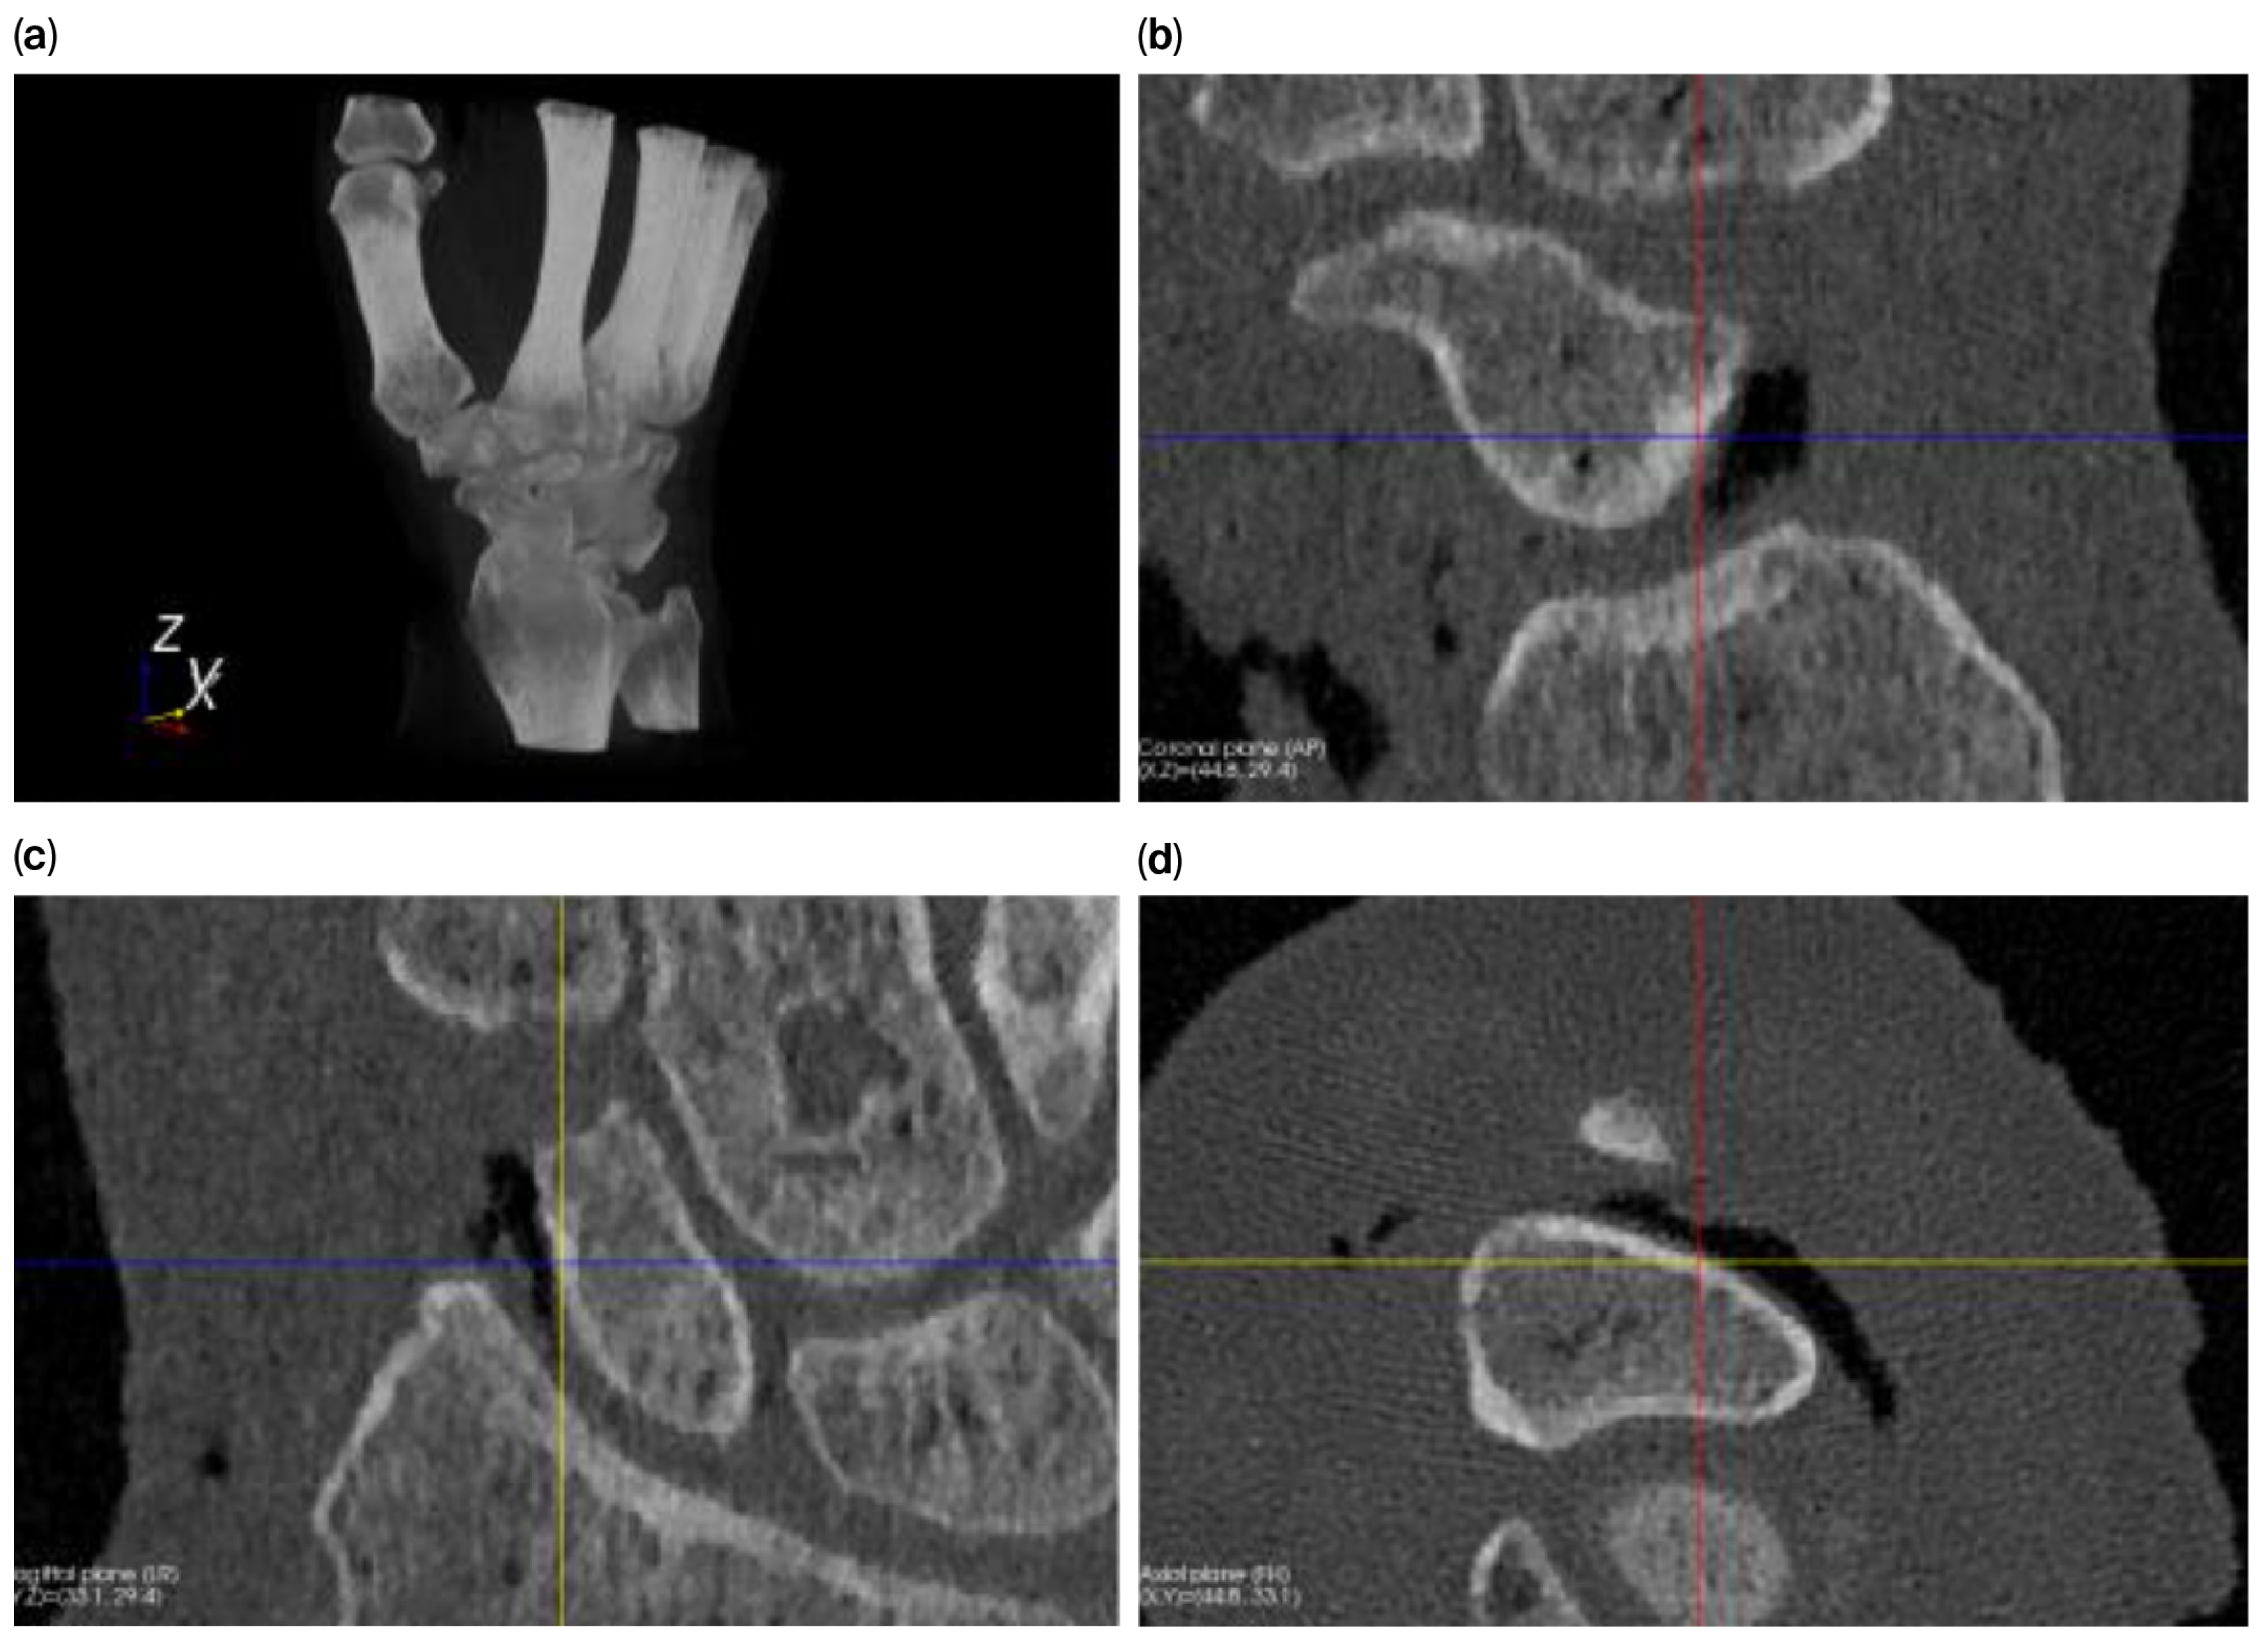

The level-set algorithm initially uses Gaussian smoothing to remove these irregularities, but applying such a smoothing filter to a thin cortical boundary may cause this layer to widen (caused by the point-spread function of the Gaussian filter kernel), which in turn causes the scaphoid object to become slightly enlarged after segmentation. Therefore, different segmentation approaches are used to answer the research questions (Figure 2) as follows:

• For investigating the size difference and reproducibility of segmentation between frozen and thawed conditions, image smoothing was carried out with rather limited parameters (σ = 0.3 mm; level-set iterations = 20), resulting in a tight-fitting segmentation.

• To achieve a smooth scaphoid object for implantation, further image smoothing was used (σ = 1.0 mm; level-set iterations = 30), resulting in a segmentation with a smooth outline. However, for the reasons outlined above, the object will become slightly enlarged. To circumvent this issue, we first changed the underlying gray-level image so that the cortical layer is no longer thin. This was achieved by first segmenting the scaphoid by region-growing and region-filling conditions (no level set) and subsequently eroding the segmented object by 0.5 mm. The masked (trabecular bone) region was subsequently replaced by a CT value of 2106 HU (an approximate intensity value of the cortical layer). As a result, the thin layer disappears, minimizing the widening effect. This adapted gray-level image was subsequently segmented as normal, as described above (σ = 1.0 mm; level-set iterations = 30).

Figure 2. Segmentation process for a smooth 3D model of the scaphoid: (a) original image; (b) segmentation using region growing and filling; (c) after 0.5 mm of erosion; (d) after filling the segmented part of the gray-level image with a value of 2106 (the approx. value of the cortical layer); (e) after region growing and filling of the modified image; (f) polygon outline; (g) slight mismatch between the outline and the underlying gray-level image; and (h) a smooth 3D representation of the scaphoid polygon.